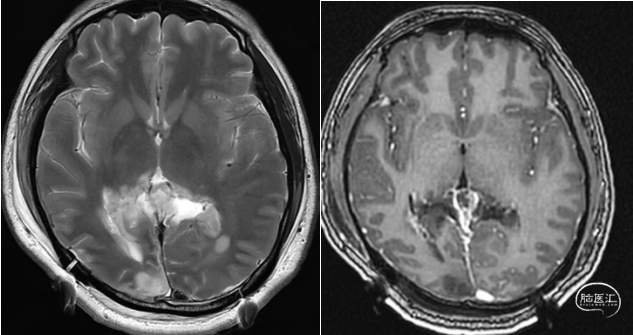

术后

本例患者影像学上表现为累及胼胝体压部的典型的蝴蝶状胶质瘤,病变累及双侧半球,非对称分布。手术均用右侧顶枕叶造瘘+左侧纵裂入路,术中先后探查和分块切除大脑镰后部两侧的病变。大脑镰后部毗邻大脑深部静脉系统,需要尽可能避免损伤Galen静脉或下矢状窦等重要结构,左侧纵裂入路可能有利于实现更好的功能保护。位于胼胝体不同部位的蝴蝶状肿瘤,由于解剖基础和功能保护的需求,采取不同的入路,从而在尽可能保护脑功能的前提下安全切除病变。

MoCA 29/30

WAB 言语正常

MMSE 28/30